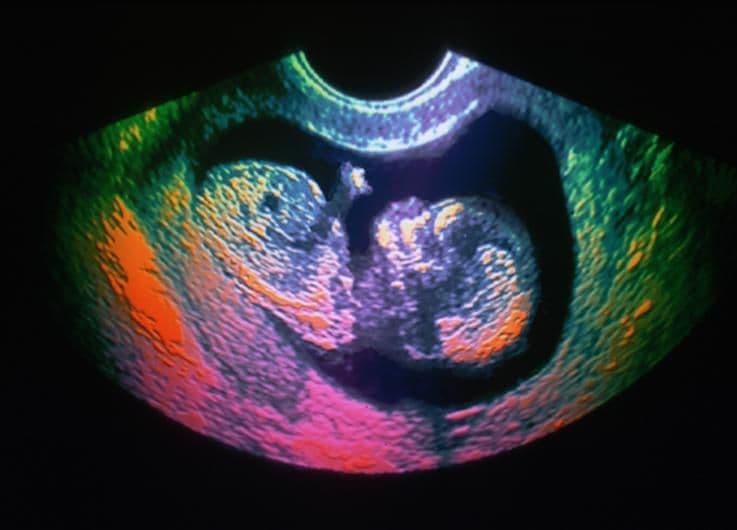

In this week, the lungs become almost fully functional and able to support the baby if delivered early. However, the baby at this time is still preterm, and will not be mature enough until 37 weeks to be considered full term.